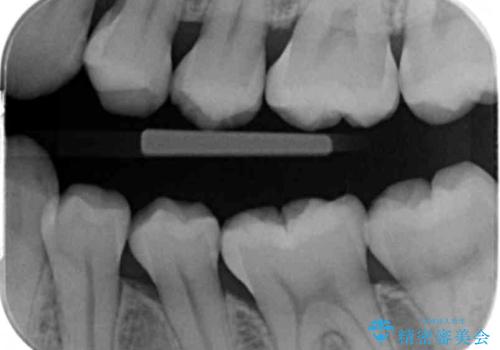

- 下の奥歯の黒ずみが気になるとのことで来院されました。

検査の結果咬む面に虫歯があることがわかりました。

削る前は小さな虫歯に見えますが、歯の中で進行しつつある虫歯でした。

虫歯が大きくなると必要な治療が増えてえしまうため早期発見、早期治療を行うことが大事になってきます。